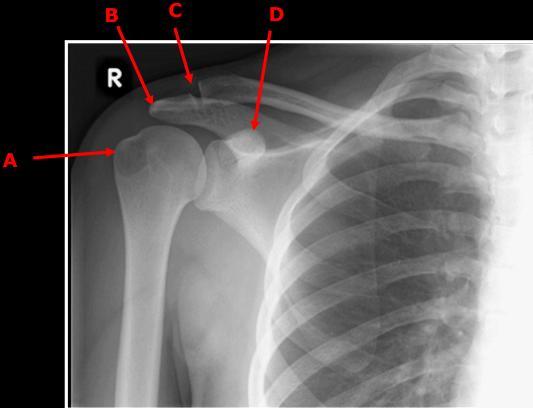

A) Greater tubercle of humerus

B) Acromion of scapula

C) AC joint

D) Coracoid process of scapula